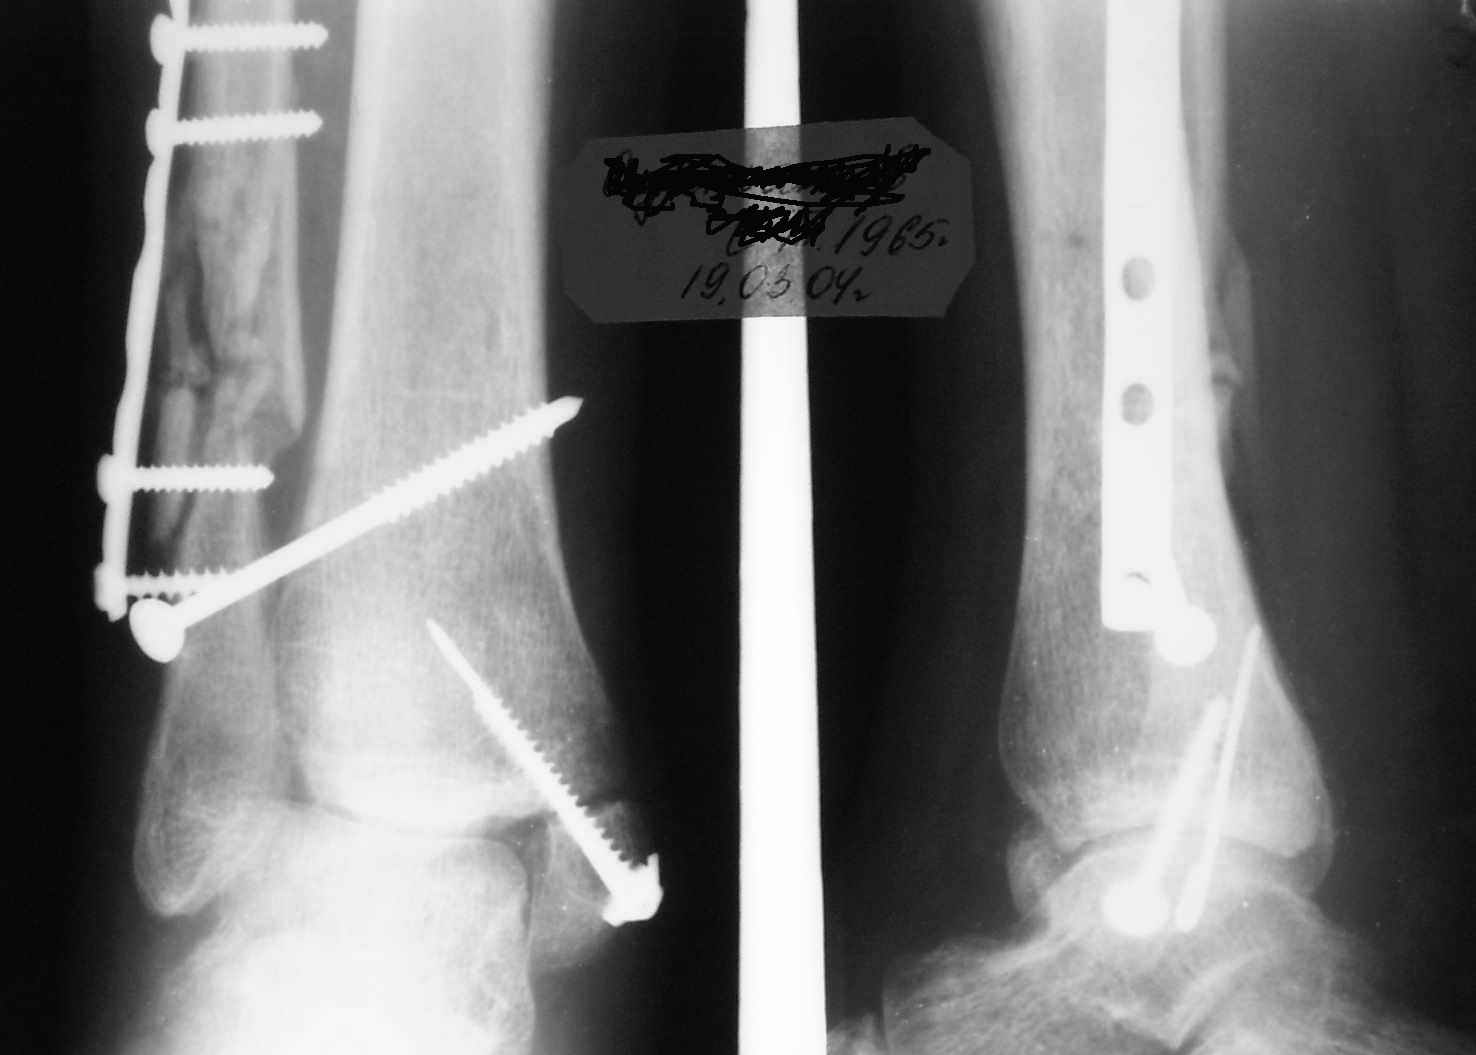

Ниже рентгенограммы

Через месяц

|

Боковой через месяц

15 ноября прямой

15 ноября боковой

15 ноября трехчетвертной

Риторический вопрос - в каком руководстве рекомендован такой способ остеосинтеза наружной лодыжки?

Очевидно, такой результат операции был запрограммирован. При невосстановленной длине и практически нефиксированной малоберцовой кости (этот кортикальный винт - как карандаш в стакане), при неустраненном подвывихе, невправленной и тоже нефиксированной внутренней лодыжке нет стабильной вилки сустава. Если такую операцию сделать даже сразу, а не через 4 месяца, то результат ожидаем

Вариант с артродезом уже обсудили. Хотя, после увиденых снимков, пессимизм насчет восстановительной операции у меня, например, несколько уменьшился. Особенного уж какого-то остеопороза не видно даже на январских снимках. Можно черед мини-доступы убрать винты, аппаратом вправить малоберцовую кость, устранить подвывих стопы. Ну а дальше фиксировать малоберцовую пластиной сзади. А может, и напряженной Y-спицей попробовать - Анатолий Федорович, как Вы полагаете? Внутреннюю - то, что осталось, если уже не получится сделать спицами и проволокой, то что-то типа пластики дельтовидной связки. А может, и не трогать ее вовсе... В общем, выбор непростой,

много факторов надо взвесить.

Если до сих ничего не сделано, с артродезом сустава в данный момент я бы повременил, на выставленных январских снимках хорошо сохранившийся сустав, а в "мортиз" (трехчетвертной) и на боковых снимках не менее 5 мм укорочение малоберцовой кости. Косые переломы лучше фиксировать пластинами, как то мы разбирали случай, где было отмечено, что это закон "таранная кость всегда следует за малоберцовой".